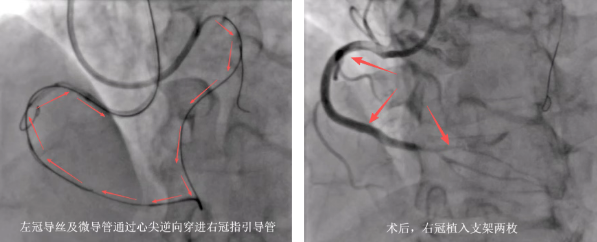

获得家属同意后,县人民医院心血管内科介入团队先尝试通过正向突破,更换多种CTO导丝均无法通过右冠闭塞病变到达远端血管真腔。而后考虑行逆向开通右冠CTO病变,在指引导管和微导管的双重支撑下,通过逆向导丝技术,在众多细如发丝的侧枝血管中反复探寻路径,多次更换具有不同性能的导丝。因为导丝和微导管的管径仅有0.3mm左右,在直径2mm的指引导管内将丝线穿进,这一操作的难度相当于裁缝拿着细线蒙着眼睛穿针眼,难度可想而知。经过反复调整方向,导丝最终顺利通过了闭塞病变。经过3小时后,终于成功完成逆向开通右冠CTO病变,于右冠远段至近端由远及近串联植入2枚支架,血管完全开通,手术成功。

心血管内科朱兴彪主任介绍:“CTO患者的冠脉闭塞时间较长,斑块往往坚硬,或伴有钙化,手术导丝难以顺利通过,且很多闭塞段后续没有明确的血管走行方向,导丝就容易穿过血管内膜甚至穿透血管,所以CTO病变行经皮冠状动脉介入治疗(PCI)的手术难度大、操作时间长、成功率低,因而CTO病变被认为是冠脉介入治疗的‘最后堡垒’。针对这种情形,一般可采用两种手术方案,即正向开通技术以及逆向开通技术。其中,正向开通技术是处理CTO病变最经典且首选的介入方法,也是所有CTO介入治疗的基石。目前我院已通过正向开通CTO病变接近50例,但是当正向介入治疗失败或者存在高风险时,就需要尝试逆向开通。值得一提的是,这两种技术可以相互补充及适时转换,通过最佳方案的选择,最终实现闭塞血管的顺利开通。而逆向导丝的操控,需要医生凭借长期‘实战’积累的敏锐触觉和丰富经验,在血管造影机的实时监视下,以毫米级的细微动作推送导丝,如同在蜿蜒曲折的血管迷宫中穿针引线。导丝前进时,需要结合压力变化、影像反馈与手感阻力综合判断,稍有不慎就可能引发血管夹层或穿孔。该患者CTO病变闭塞为两节段,更是增加了手术的难度和风险。”